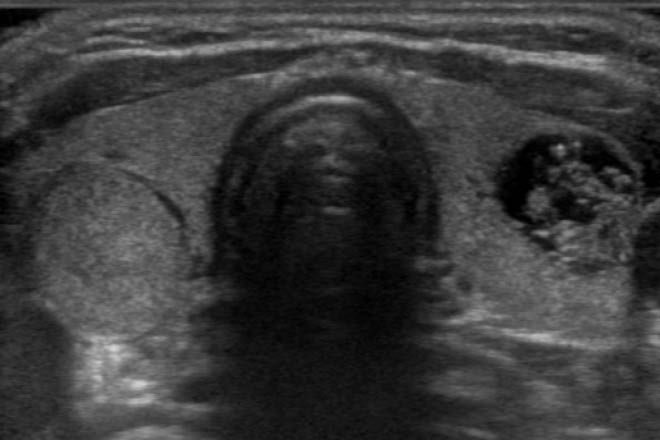

La aplicación del ultrasonido en el estudio de la glándula tiroides es de gran utilidad como método confiable. Su correcto uso para diagnóstico presuntivo del cáncer de tiroides y control luego de su tratamiento quirúrgico, es de fundamental importancia en el seguimiento de esta patología, siendo el mejor método para el estudio del cuello operado.

La American Thyroid Association (ATA) sugiere el uso del ultrasonido cervical en el seguimiento de pacientes operados de cáncer tiroideo y la realización de punción aspiración con aguja fina (PAAF) cuando los hallazgos indican una posible recurrencia.

La PAAF guiada por US es el «gold estándar» para el diagnóstico y tiene una sensibilidad del 60% al 90%, especificidad del 100%, valor predictivo positivo del 100% y un valor predictivo negativo del 80%, alcanzando una exactitud del 85%.

La PAAF guiada por US es una técnica mediante la cual se puede diagnosticar cáncer en lesiones entre 3 a 5 mm.

El estudio ecográfico debe comprender la logia tiroidea en el caso de tiroidectomía total y del remanente cuando es subtotal, así como la exploración de todos los territorios ganglionares del cuello.